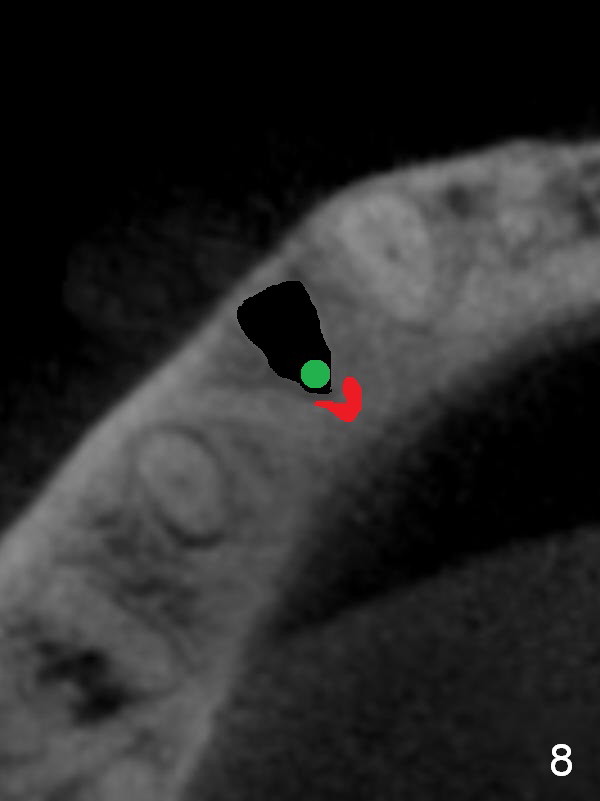

CT sagittal section shows that it is possible to place 4.5x20 mm implant (Fig.6). Axial (Fig.7) and coronal (Fig.9) sections show that the lingual (L) plate is much thicker than the buccal (B) one. To prevent the implant being buccally deviated, a Lindermann bur is used after extraction (black area in Fig.8,10) to remove ~ 1mm bone from the lingual plate (red area in Fig.8,11). A 2 mm pilot drill is placed as lingual as possible (green in Fig.8,11). If the implant (Fig.12) starts to deviate buccally while being placed, remove it from the osteotomy and remove more bone from the lingual plate. Place the implant again and monitor the trajectory tightly.